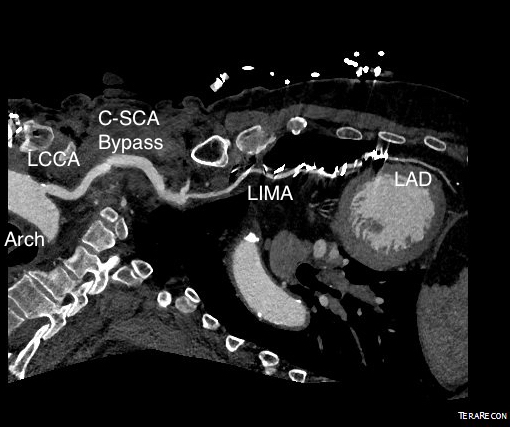

The EVAR was performed percutaneously. No endoleak was detected by completion arteriography (figure). He was soon discharged and was grateful. In followup, CT scan showed excellent coverage of the proximal and distal zones and absence of type III endoleaks. There was increased density to suggest a type II leak, but his inferior mesenteric artery was not the source of it. over a three year period, his aneurysm sac continued its 2-3mm of annual growth despite the presence of the the stent graft.

While CT failed to locate this endoleak, abdominal duplex ultrasound did showing flow from a small surface vessel (duplex below, figure at beginning of post). It was not the inferior mesenteric artery which can be treated endovascularly (link) or laparoscopically (link). CT scan suggested that it was one of those anterior branch vessels that one would encounter in exposing the aorta. Usually these were higher up as accessory phrenic arteries, but these fragile vessels, larger than vasovasorum, but smaller than named aortic branches, are seen feeding the tissues of the retroperitoneum.